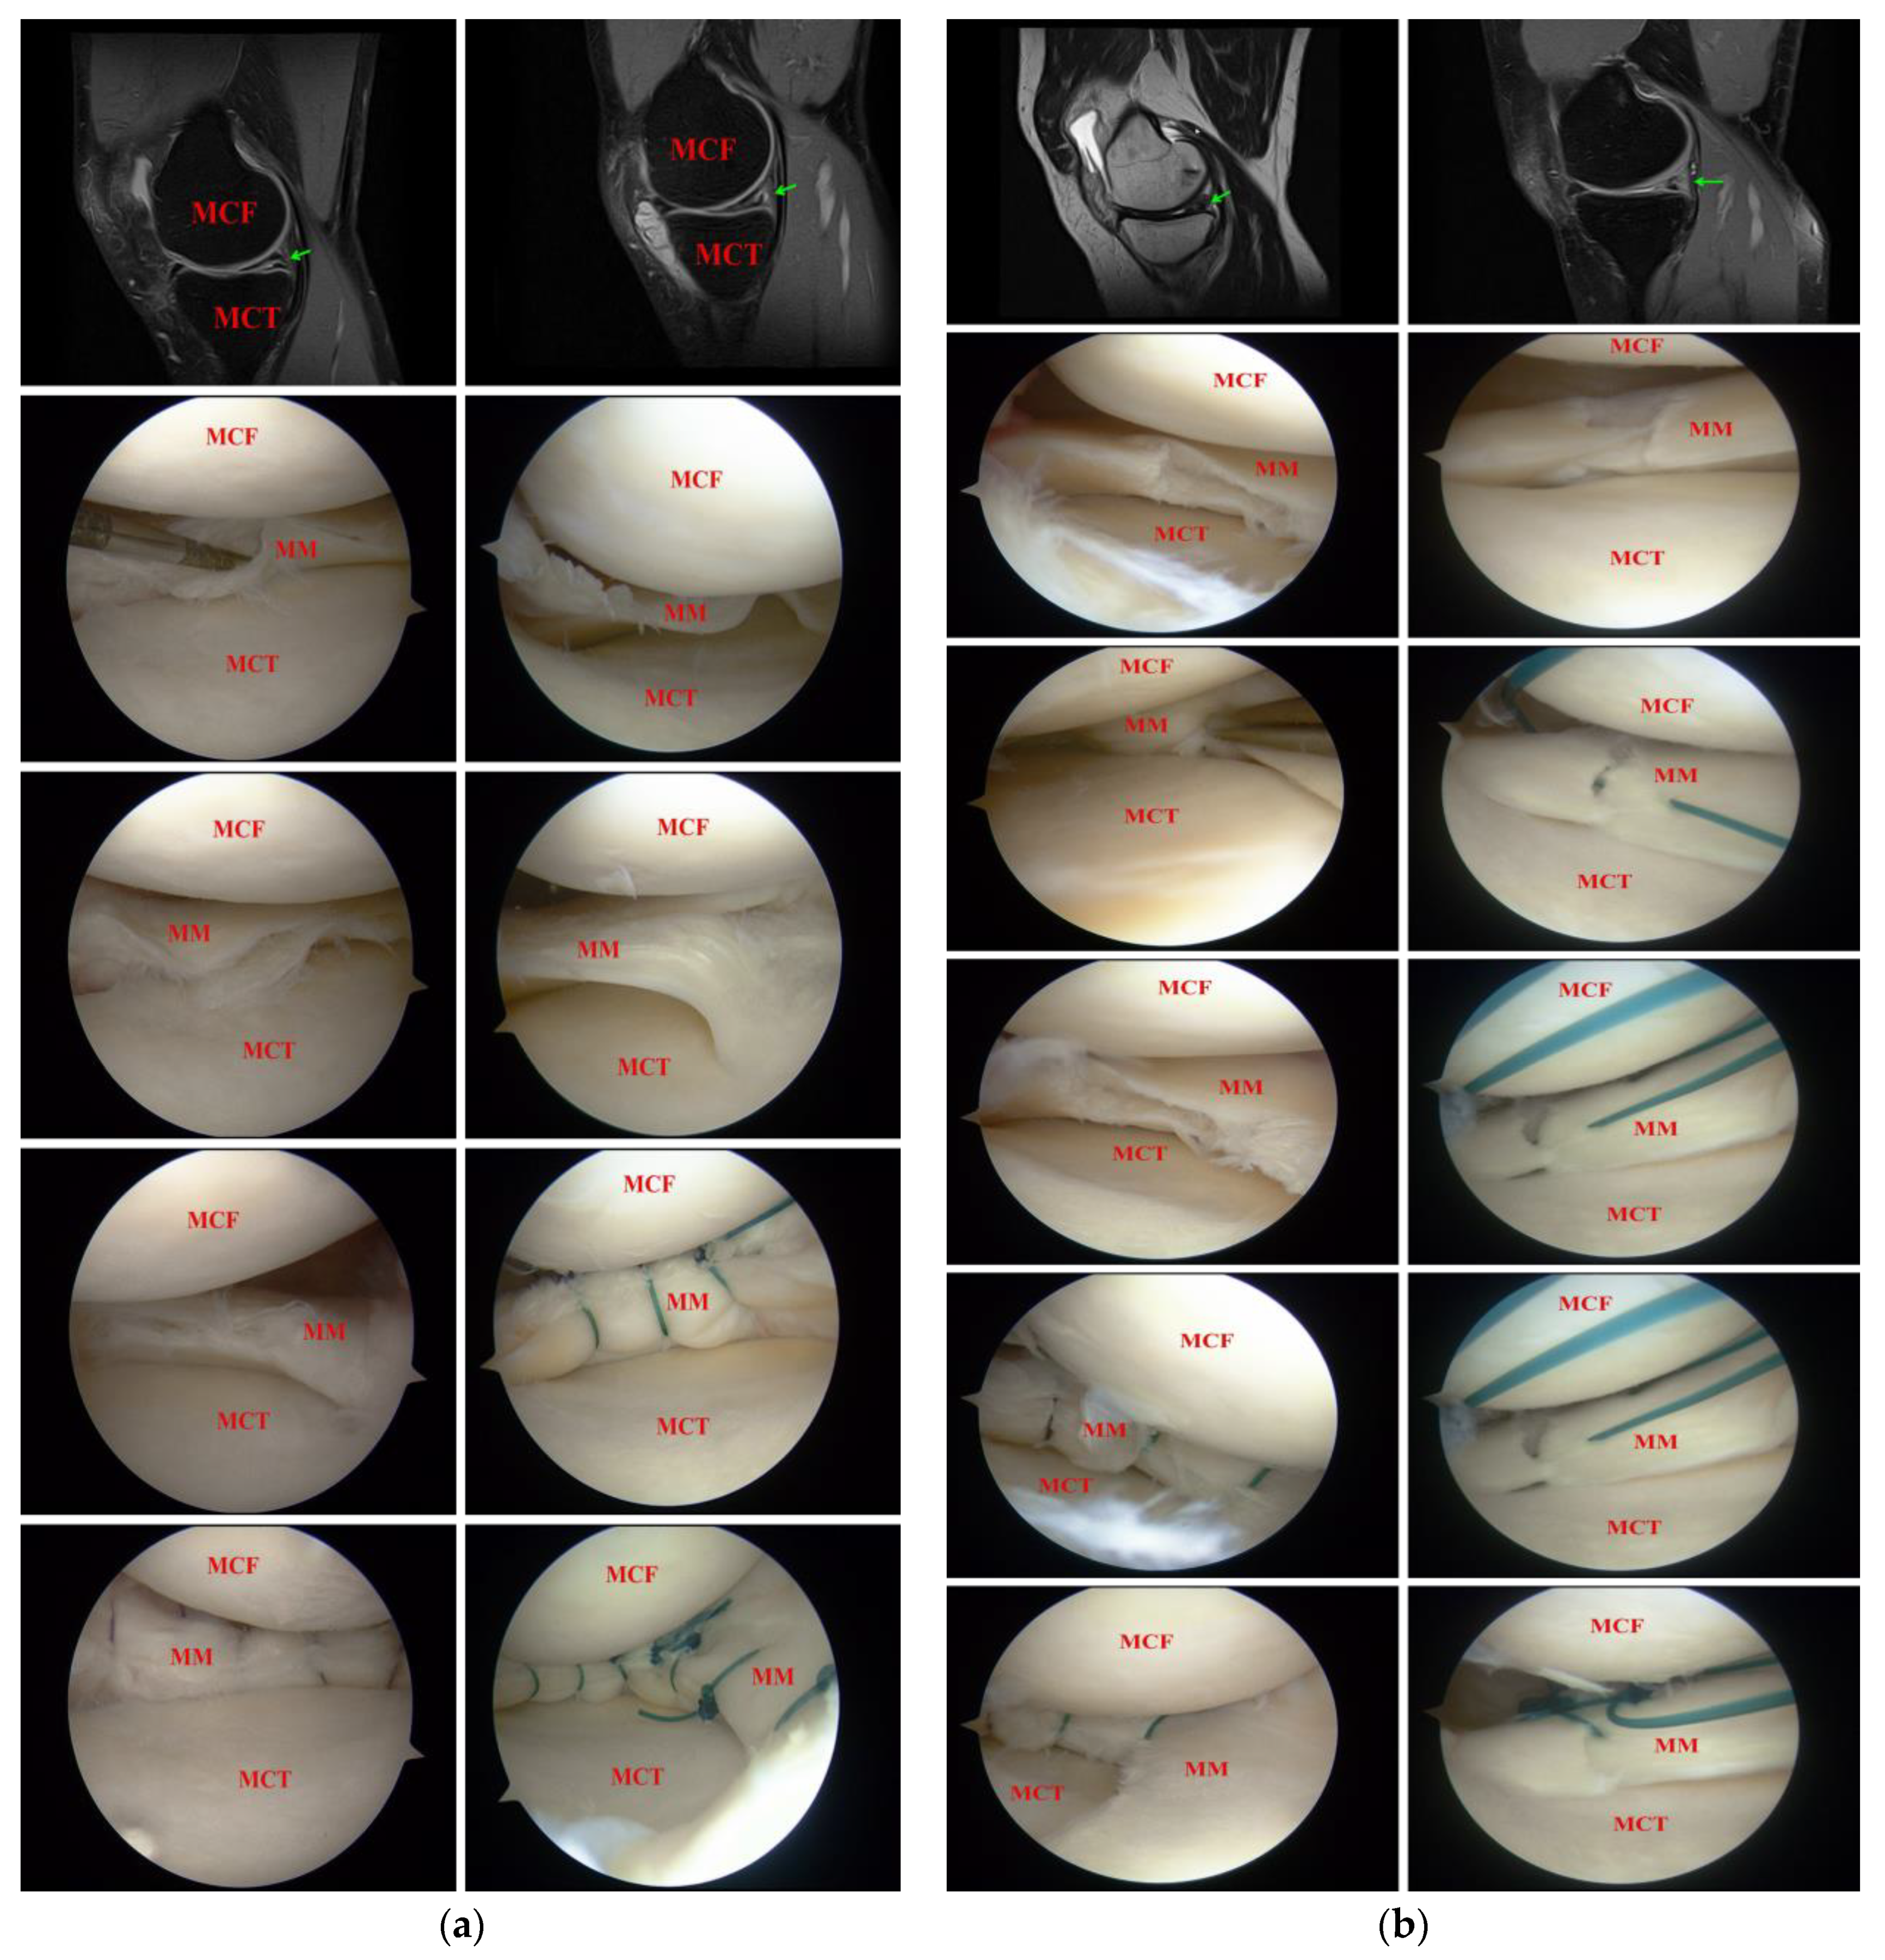

2.2. Surgical Treatment